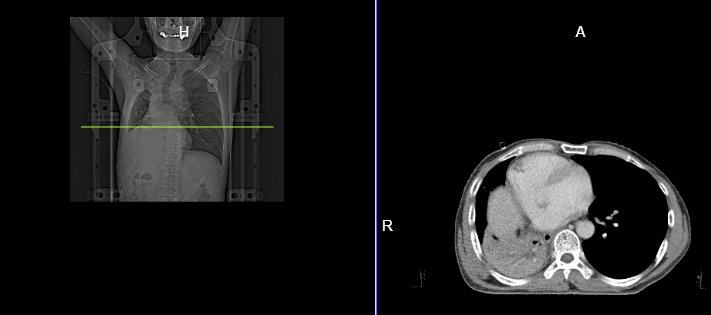

咳嗽、胸闷、气短 30年老烟民不相信自己会得肺癌 近日,医院来了一名50岁的王先生,述说自己间断性咳嗽、咳痰1年多,最近一个月感觉自己胸闷气短症状加剧,于是去当地医院检查,考虑为右肺气胸,随后行胸腔闭式引流术,排空气体后,王先生胸闷气短症状并没得到缓解。 于是到上一级医院进一步治疗,通过纤支镜检查时发现右主支气管有肿物,活检检查显示为鳞状细胞癌,并随即行气管支架植入术。但术后没多久再次出现气胸,如此反反复复,王先生很是苦恼,甚至不相信自己患了肺癌,认为自己又没咳血,怎么就会是肺癌啦? 其实肺是一个哑巴器官,很多时候早期肺癌并不会向身体报警,但如果你同时出现下面这些症状,就要提高警惕,及时检查! 1、胸部感染并且伴随有长期反复感染的症状; 2、无缘无故地喘息和呼吸急促; 3、胸部或肩部疼痛,并且长期没有好转; 4、嗓音嘶哑并且持续三周以上; 5、长期咳嗽、体重减轻、感觉极度疲倦; 7、杵状手指:手指末端形状发生改变,出现变大或变圆的症状; 8、脸部、颈部、腋下出现肿胀; 久治不愈的肺癌症状 在放射治疗下销声匿迹 “命途多舛”王先生为寻求更好的治疗方法,经多方打听,找到了在肺癌治疗方面颇有造诣的昆明医科肿瘤医院骆建华主任团队,寻求进一步诊治。 骆主任在详细了解王先生病情之后,评估患者气道肿瘤暂无手术条件,凭借自己多年来熟用放射治疗救治患者的丰富经验,为王先生治疗了详细的放疗计划。 放疗结束后,王先生咳嗽、胸闷、气短等不适情况明显好转,恢复状态良好。通过CT影像资料显示,在放射治疗的帮助下,王先生的肺部肿瘤已得到有效控制。 放疗前 放疗后 科普小结 放疗在肺癌治疗中大有可为 由于王先生肿瘤位置的特殊性,手术不但不能一劳永逸,还存在巨大风险,这种情况下,选择放射治疗的确是一个明智的决定。 近年来,随着科技高速发展,放疗在肺癌的临床应用中有着不可替代的作用,其“高精度、高剂量、高疗效、低损伤”的特点,能够追着肿瘤细胞“指哪打哪”。 特别适合高龄、不具备手术条件或其他因素身体耐受力差的患者,可通过放疗减轻患者痛苦、延长患者生存时间、降低复发及远处转移的风险,并且还能大大缩短患者平均住院日,减少患者住院费用,为广大肿瘤患者提供了新的希望!